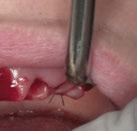

y lo que se pudo preservar del hueso malar. Se añadió una malla sinterizada infraorbitaria para dar volumen a la mejilla y se planificaron dos brazos de conexión que emergieran en las posiciones 24 y 26 de forma subgingival (Figuras 8 y 9). La superficie interna que apoyaba en el hueso era de titanio microrrugoso, y la superficie externa y conectores de titanio pulido y hexágono externo universal (Figuras 10 y 11). La cirugía se hizo bajo anestesia general en infiltración con anestesia local (4% articaína, 1:100.00 epinefrina), levantando el

colgajo cutáneo de la mejilla por vía intraoral, preservando el colgajo temporal para no comunicar con el remanente de la cavidad naso maxilar (Figura 12). Se emplearon 10 tornillos de osteosíntesis de 1,9 mm y la estabilidad primaria obtenida fue excelente (Figura 13)